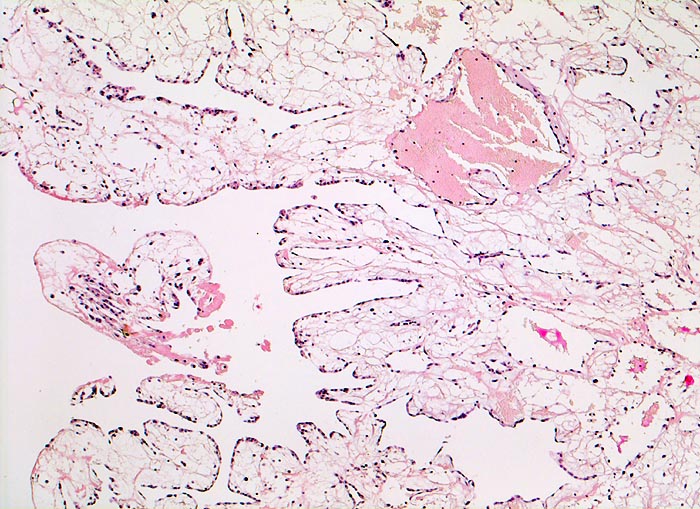

PathoPic ID 3005 - Vorhofmyxom

Vorhofmyxom

benigner Tumor

Herz Vorhof

Kardiovaskuläres System

Tumor aus fingerförmigen Formationen mit ödematösem myxoidem Stroma. Fokale Stromablutungen.

Histologie

50